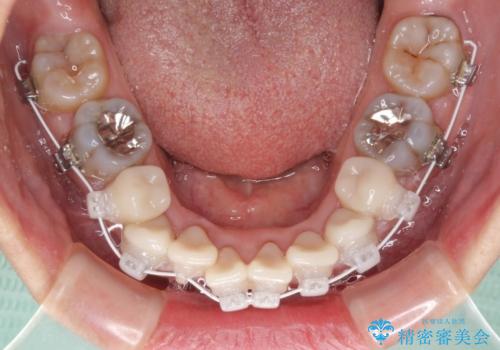

- 矯正装置

- 審美装置

- 1年3ヶ月

- 小さいころからの歯の変色と矯正治療の後戻りを気にして来院された患者様です。

気になる変色歯を仮歯に変え、その後歯列不正を矯正治療で改善し、最後にオールセラミッククラウンにて補綴治療することとしました。